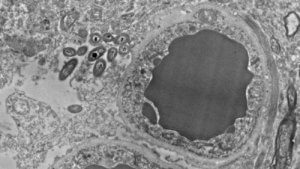

Dr. Rosalinda Roberts og hennes team fra avdelingen for psykiatri og atferdsnevrobiologi ved universitetet i Alabama i Birmingham er ansvarlige for dette funnet. De studerte hjernen til 34 personer. Halvparten av deltagerne i studiet var friske personer, og den ande halvparten hadde schizofreni. Videre gjennomførte de en parallell studie på labratoriemus, slik at de kunne utelukke at bakteriene kun dukket opp post mortem, eller om det kunne oppstå feil på grunn av kontaminering.

I begge studiene observerte forskerne tilstedeværelsen av bakterier i både hjernene til mennesker og mus, i ikke-smittsomme eller traumatiske situasjoner. Faktisk fant de disse bakteriene i flere områder av hjernen. Hovedsakelig ble de funnet i substantia nigra, hippocampus og prefrontal cortex, og veldig små mengder i stratium. I tillegg viste ingen av de undersøkte hjernene noen tegn på betennelse.

Hovedbilde gjengitt med tillatelse fra Rosalinda Roberts, Courtney Walker og Charlene Farmer.